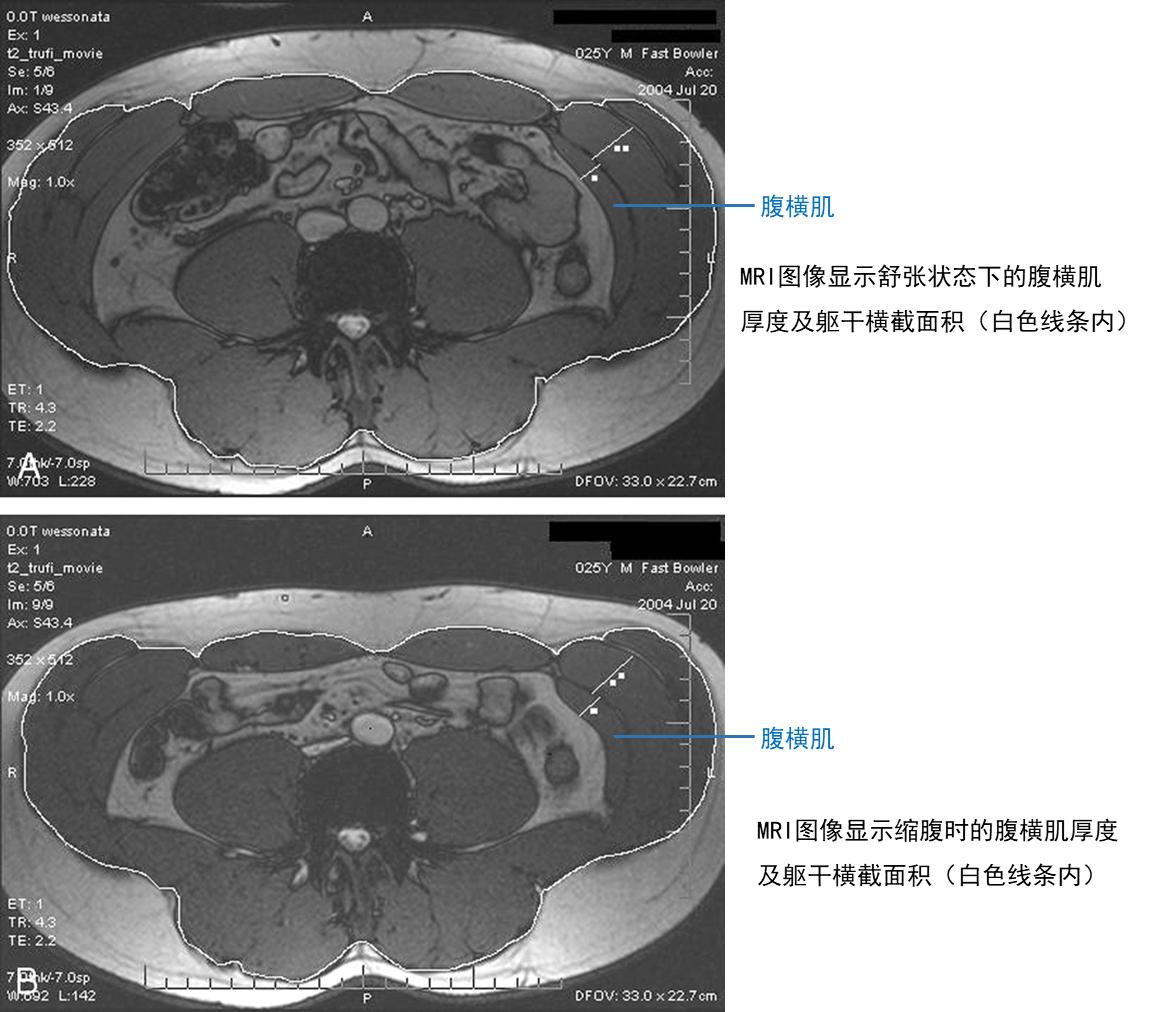

从形态上看,腹横肌的肌纤维呈水平走向,就像腰带一样横向环绕腹部。当它收缩时,会展现出三个重要变化:增厚、缩短、侧向滑动。通过 MRI 观察发现,腹横肌在收缩时(比如做 “缩腹” 动作),厚度会从静息时的 0.71 厘米增加到 1.08厘米,同时躯干横截面积会从 393.90 平方厘米缩小到 362.61 平方厘米 —— 相当于给腹腔 “收了个紧”,这种变化能直接提升腹内压力,就像给脊柱加了一个 “内部支架”,减少腰椎的晃动。